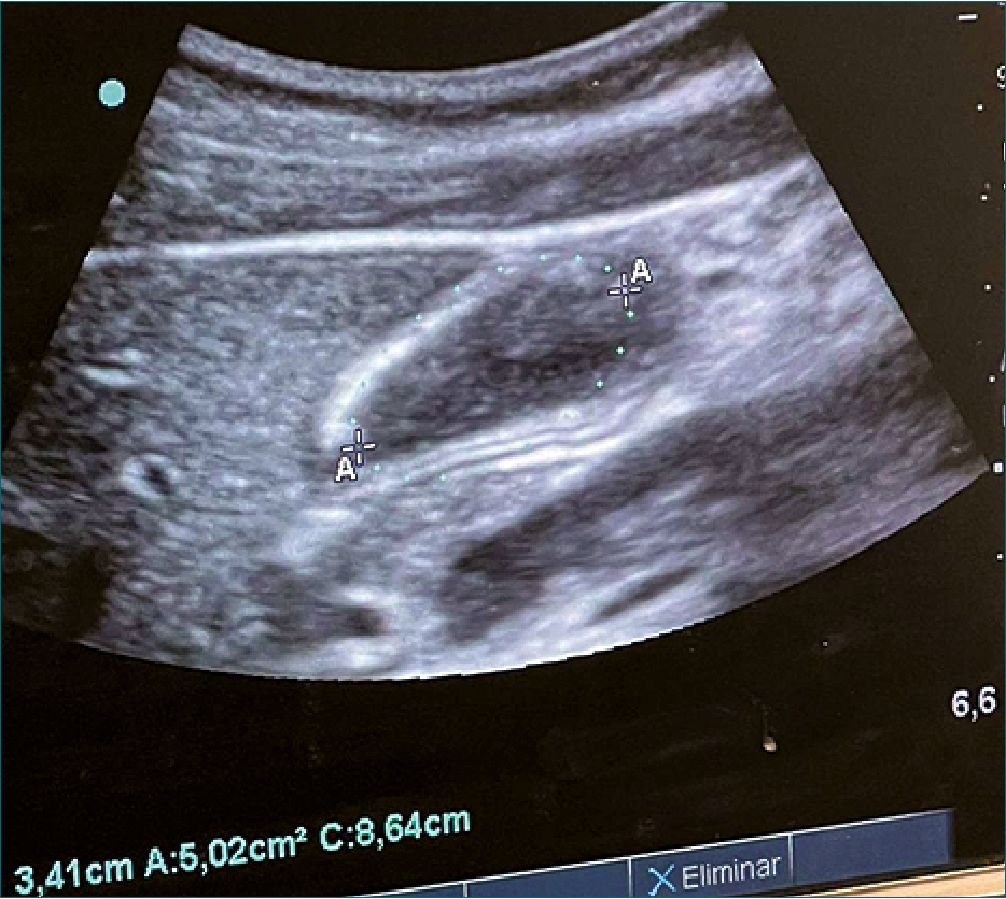

Figura 11. Medición del CSA del antro gástrico. CSA: cross sectional área.

Cuantitativo

Es necesario contar con un software que mida el área del volumen gástrico (Figura 11), cabe mencionar que de observarse estomago lleno, no hay necesidad de medir lo obvio. Se mide en el área más externa como se observa en la imagen y se correlaciona con la Tabla 6, en la cual ya se encuentra aplicada la formula descrita de: volumen (ml) = 27 + 14.6 x CSA del DLD – 1.28 x Edad[26]. Se recomienda utilizar la tabla para mayor practicidad[26].